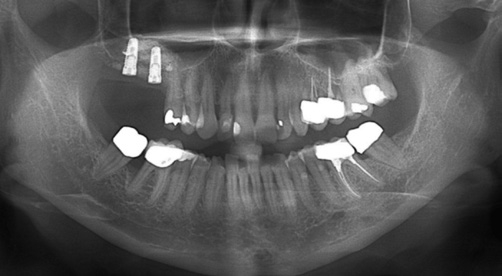

Die allgemeinmedizinisch gesunde Patientin befand sich aufgrund ihrer Grad-IV-Parodontitis seit 2013 in einem engmaschigen parodontalen Recall. Trotz der starken parodontalen Destruktion lagen stabile Verhältnisse vor. Ende 2016 stellte sich die Patientin mit Beschwerden an Zahn 16 vor. Dieser reagierte negativ auf die Sensibilitätsprobe und wies einen Furkationsgrad 3 auf. Zudem zeigte sich röntgenologisch eine apikale Aufhellungszone. Da bei dem Nachbarzahn 17 ebenfalls ein Furkationsgrad 3 bei einem Lockerungsgrad I vorlag, wurden in Absprache mit der Patientin Zahn 16 und 17 operativ entfernt. Die Patientin wünschte eine festsitzende, implantologisch-prothetische Rehabilitation und lehnte eine herausnehmbare Versorgung ab.

Nach einer Abheilzeit von 10 Wochen wurde im Rahmen der präimplantologischen Diagnostik aufgrund der Komplexität der Defektsituation im 1. Quadranten regio 16 und 17 neben der klinischen Untersuchung eine DVT-Aufnahme angefertigt. Es zeigte sich ein transversaler und vertikaler Knochendefekt mit einer Restknochenhöhe von teilweise nur 1 mm. Zu beachten war auch die Höhe des Knochenlagers, das sich teilweise auf Höhe des Apex des Nachbarzahnes 15 befand (Abb. 1a und b). Dieser dreidimensionale Defekt sollte durch einen externen Sinuslift nach kranial sowie eine ventrale horizontale auflagernde Augmentation ausgeglichen werden. Hierfür wurde mit dem DICOM-Datensatz der DVT-Aufnahme ein virtuelles Modell hergestellt, welches die Planungsgrundlage für das Augmentationsvolumen darstellte (Abb. 1c). Anhand dieser Daten und in Abstimmung mit dem Behandler stellte die ReOss GmbH ein patientenindividuell gedrucktes Titangitter für die Augmentation her.

Die Zahnentfernung im stark parodontal geschädigten Gebiss führt zu deutlichen Weich- und Hartgewebsdefiziten. Im Bereich der Kieferhöhle lässt sich zwar mit einem externen Sinuslift das Hartgewebsdefizit nach kranial vorhersagbar augmentieren, jedoch führt dieses Verfahren bei starken Atrophien zu einer vergrößerten Implantat-Kronenlänge und zu unterschiedlichen Emergenzniveaus der Restbezahnung und der Implantate. Um daraus resultierende parodontalhygienische Schwierigkeiten zu vermeiden, ist eine vertikale Rekonstruktion sinnvoll. Eine denkbare Alternative zu dem in diesem Fall hergestellten patientenspezifischen CAD/CAM-Gitter als Auflagerungsplastik wäre eine Blockaugmentation mit einem im Bereich der Linea obliqua entnommenen kortikalen Knochenblock. Jedoch ist die lagestabile Fixation des Blockaugmentats aufgrund der Restknochenhöhe von etwa 1 mm zum Sinus maxillaris schwierig und unsicher. Weitere denkbare Techniken zur vertikalen Augmentation wären eine Segmentosteotomie oder eine Distraktionsosteogenese, welche aber aufgrund des direkt kranial liegenden Sinus maxillaris nicht anwendbar sind.